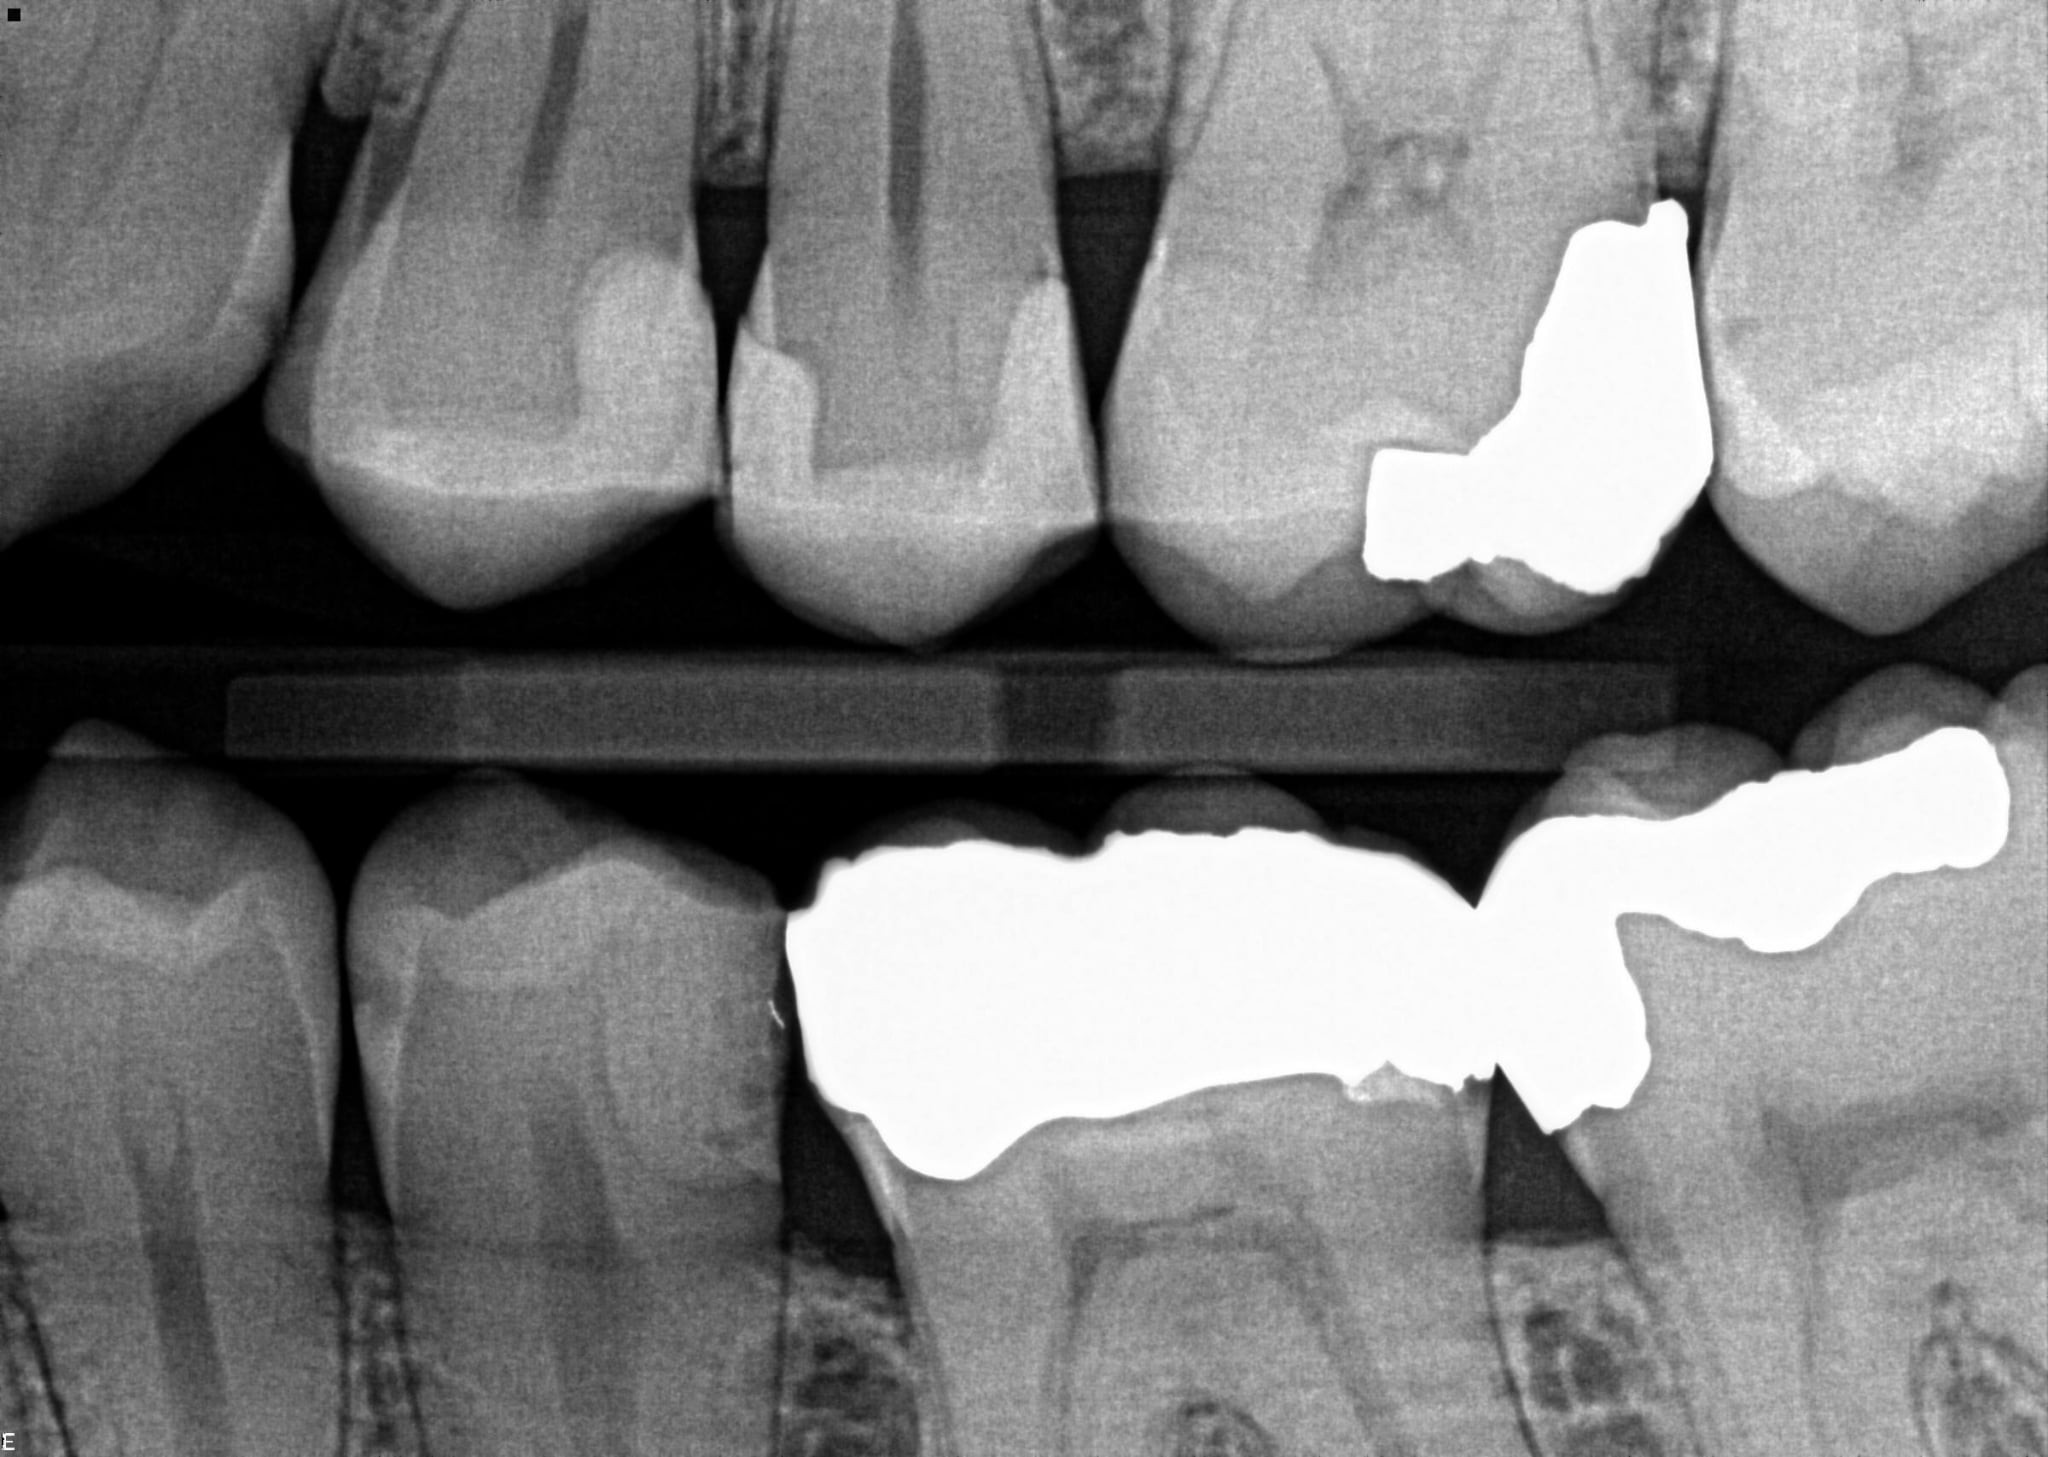

7. In the X ray bellow for which jaw periodontal bone loss is evident?

8. In the X ray bellow for which jaw periodontal bone loss is evident?